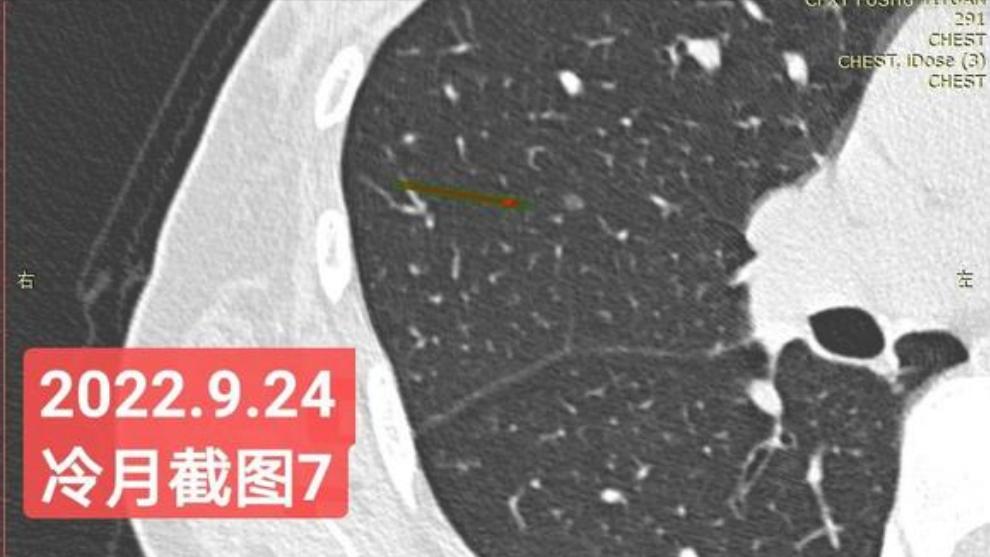

我是21年7月做肺部CT,报告给报出0.5厘米肺结节。(但大夫说,20年就已经有那个肺结节了,因为小,报告没给报)。自发现肺结节后,吃了四个月中药,结节没有缩小,反而增大了。今年8月1日开始到现在,又吃了近两个月的蒙药了。 结节还是没有缩小,反而在增大。21年7月到现在,复查过3次肺部CT了。结节一直在增大。最近一次复查时间是2022年9月24日。

上次找戴主任贴吧咨询过,主任说我右肺下叶那个结节高危,距离上次CT,到现在三个月复查肺部CT。所以9月24日又复查做了肺部CT。

右下肺结节高危,肺窗已经到亚实性阶段CTR>0.5,纵膈窗可见实性,目前已经不属于异质混磨,而且PSN亚实性结节。